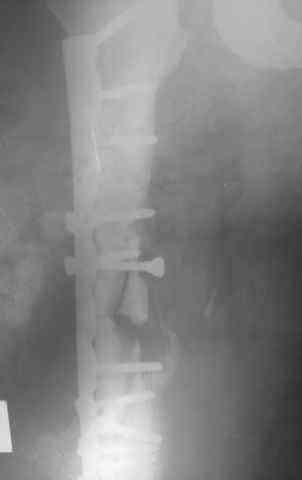

Несрошийся открытый фрагментарный,оскольчатый,перелом в/с/3 правого бедра |

Несрошийся открытый фрагментарный, оскольчатый, перелом в/с/3 правого бедра с размозжением мягких тканей. Состояние после ПХО,МОС,ВО ЧКФ стержневым АВФ. 10.10.09.Заживление раны per prima. Операция:16.12.09,открытый накостный МОС,аутокостная пластика(из крыла подвздошной кости)правого бедра. После п/о периоде заживление раны вторичным натяжением (на 5-е сутки распущены швы, после очищения раны наложины вторичные швы) На этапных RO-гр:остеолизис костного трансплантата и дистального фрагмента перелома бедра. Вопрос:дальнейшая тактика лечения-БИОС аутокостная пластика (трансплантат на сосудистой ножке М/Б кости). Билокальный остеосинтез по Илизарову с остеотомией подвертельной и надмыщелковой области бедра. Мозможен ли аутотрансплантат без сосудистой ножки? Чем улучшить васкуляризацию? Декортикация? Тактика выжидания остеолизиса, а затем оперативное лечение.